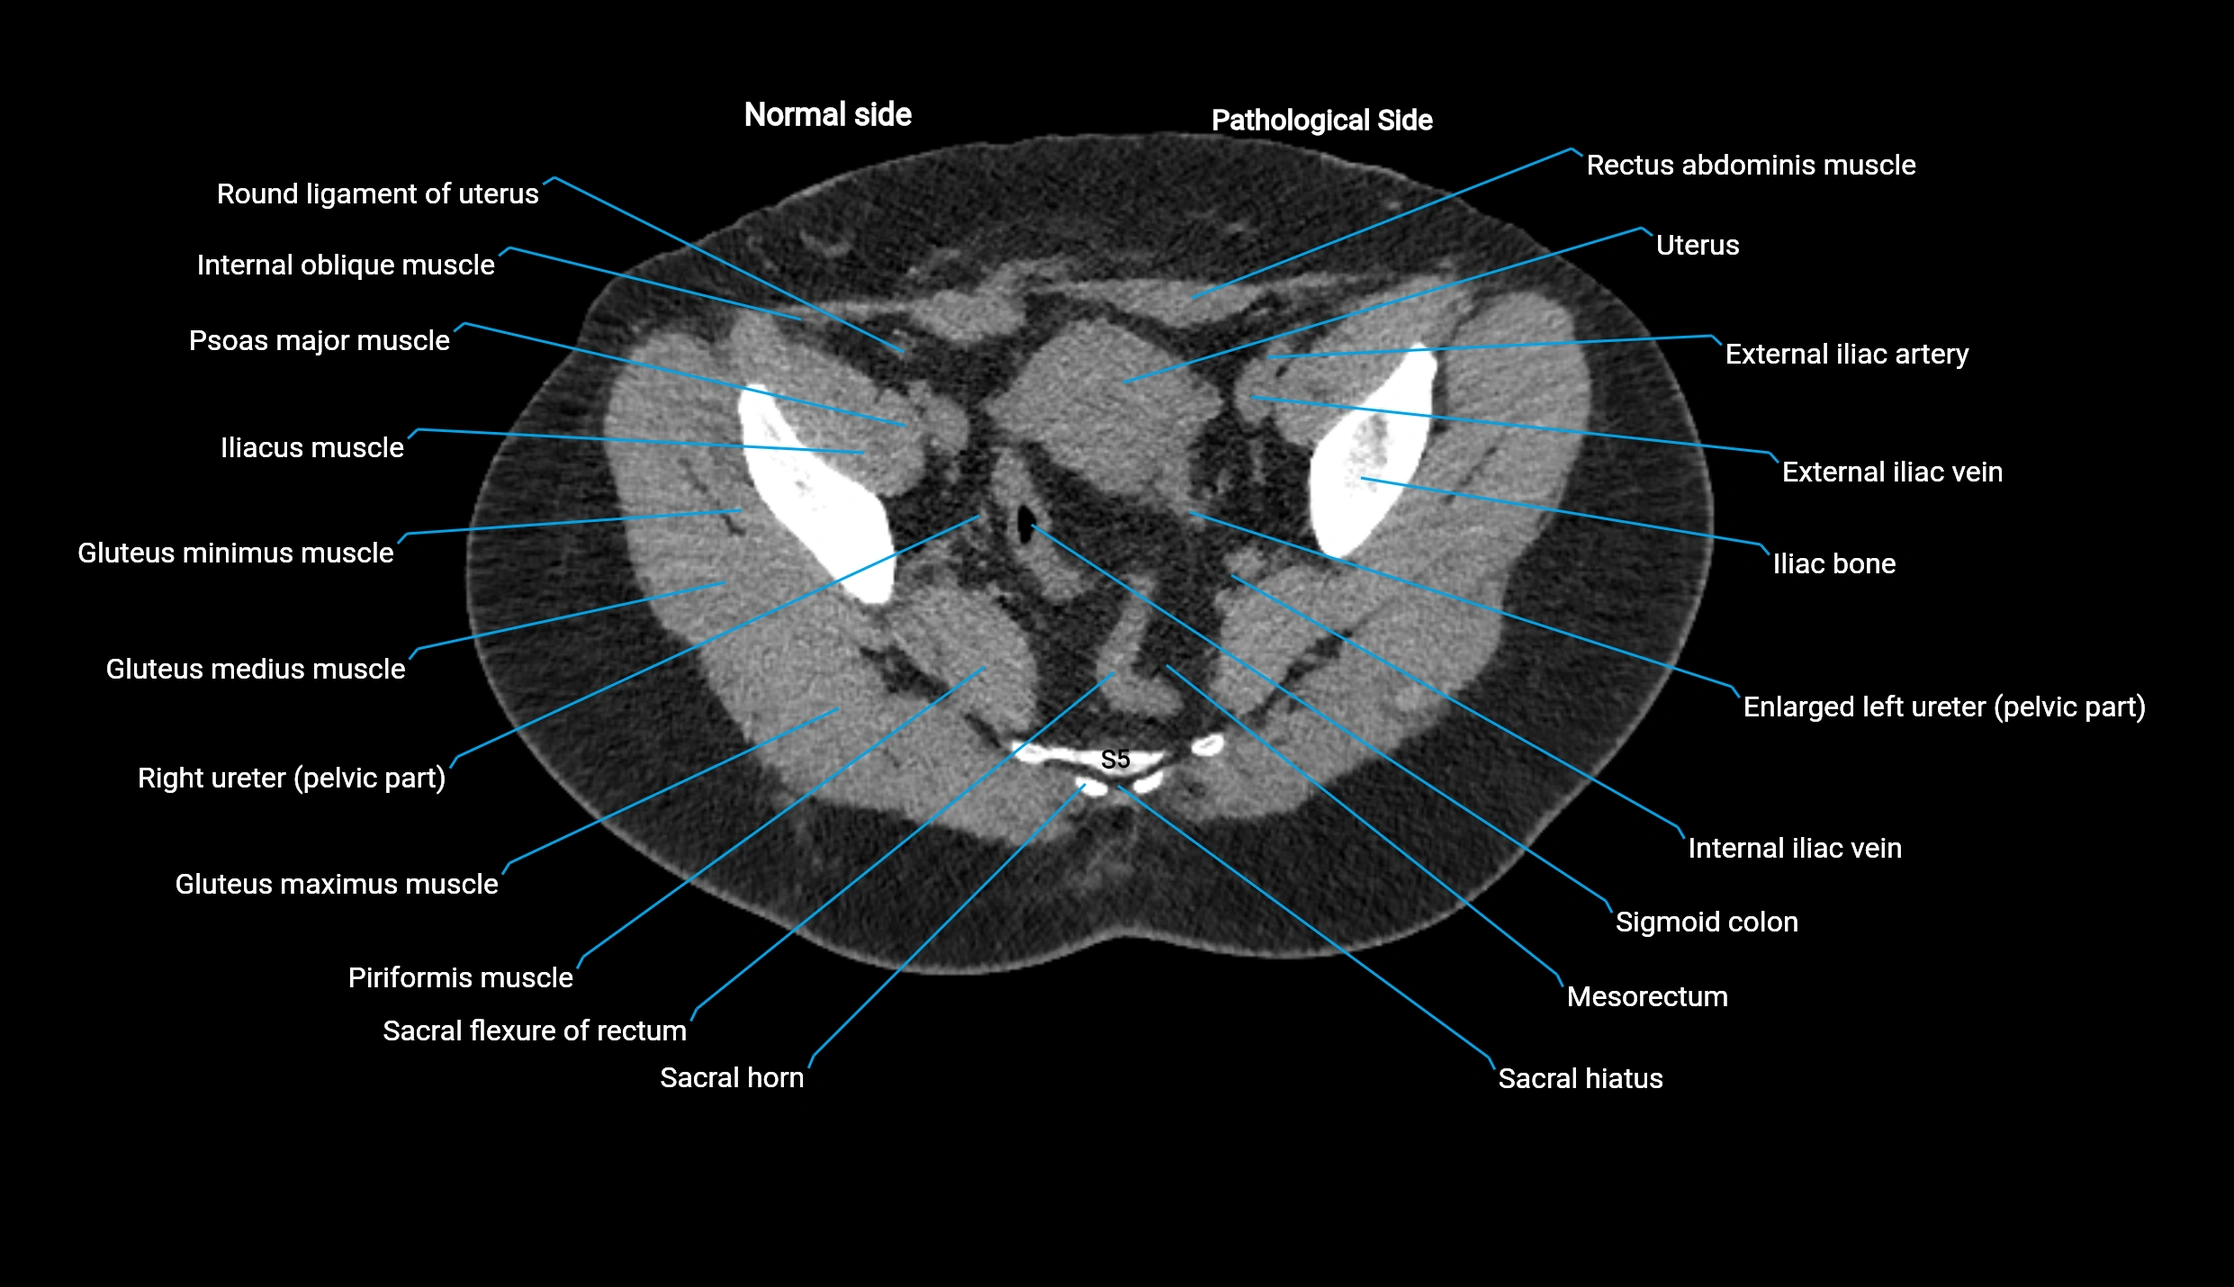

CT image

image